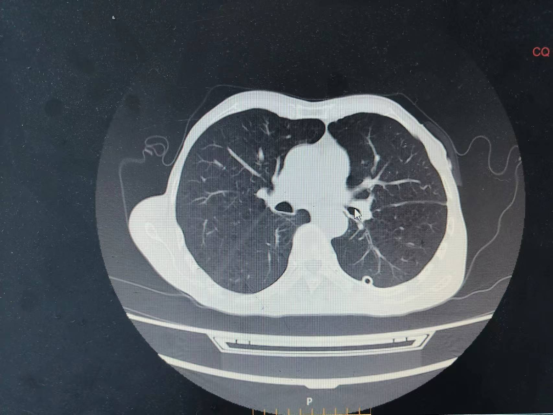

术后